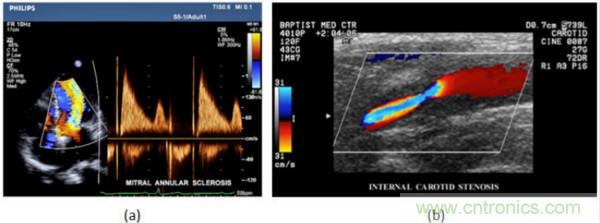

在CW和PW多普勒模式中,流信息是從一個(gè)聚焦聲束中獲得的,類似于A模式成像。在20世紀(jì)80年代,研究人員基于彩色多普勒技術(shù)完成了血流分布的二維信息可視化。彩色多普勒處理也是基于B模式/PW模式信號(hào)路徑。從感興趣區(qū)域收集多幀RF數(shù)據(jù)。由于感興趣區(qū)域中的血液流動(dòng)導(dǎo)致圖像幀之間存在數(shù)據(jù)差異。相域中的自相關(guān)和時(shí)域中的互相關(guān)兩種算法可從RF數(shù)據(jù)中提取數(shù)據(jù)方差(即血流速度和方向信息):。根據(jù)預(yù)定義的顏色漸變條相應(yīng)地映射包括速度和方向的血流信息。通常,藍(lán)色和紅色代碼分別識(shí)別朝向和遠(yuǎn)離換能器移動(dòng)的血流。當(dāng)流速增加時(shí)使用更亮的顏色,反之亦然。顏色映射的2D分布始終疊加在B模式圖像上,以實(shí)時(shí)同時(shí)顯示個(gè)體解剖結(jié)構(gòu)和血流。它對(duì)于診斷心血管疾病,如血管閉塞和心臟瓣膜反流,極其有用。典型的彩色多普勒圖像如下圖所示,(b)顯示頸動(dòng)脈狹窄引起的血流流速變化。

超聲系統(tǒng)的信號(hào)鏈設(shè)計(jì)注意事項(xiàng)

圖7.彩色多普勒成像:(a)以彩色多普勒和CW模式獲得的圖像(由Philips提供); (b)顯示頸動(dòng)脈狹窄的彩色多普勒(由GE提供)